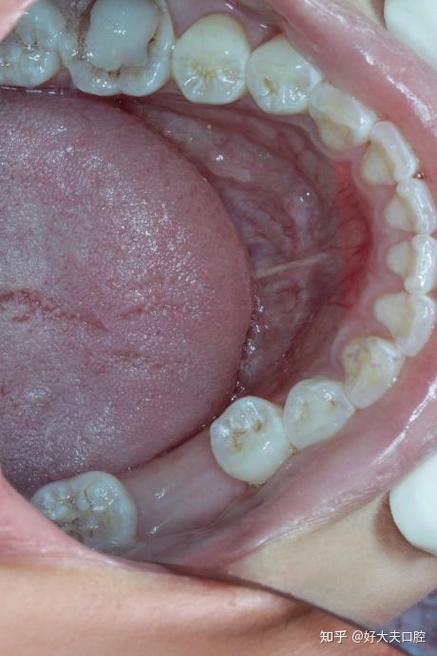

尼古丁会导致血管收缩,减少牙周组织的血液供应,降低局部抵抗力,矫正器(如牙套、托槽)本身会遮挡牙面,增加清洁难度,若此时吸烟,焦油等物质会更容易附着在牙齿和矫正器周围,形成菌斑堆积,菌斑中的细菌会引发牙龈炎(表现为牙龈红肿、出血),进一步发展为牙周炎(牙周袋加深、牙槽骨吸收),牙周组织一旦受损,牙齿移动会变得缓慢甚至停滞,矫正效果大打折扣,严重时甚至可能导致牙齿松动。

烟草中的焦油、尼古丁等色素物质会渗透到牙齿表面的微小孔隙中,导致牙齿变黄、发褐,矫正时,托槽、弓丝等附件会遮挡部分牙面,但附件周围的牙面更容易色素沉着,拆除牙套后可能出现“白斑”(未被染色的区域)与黄褐色斑块形成鲜明对比,严重影响美观,矫正器本身也可能因烟草成分发生变色,影响整体口腔观感。